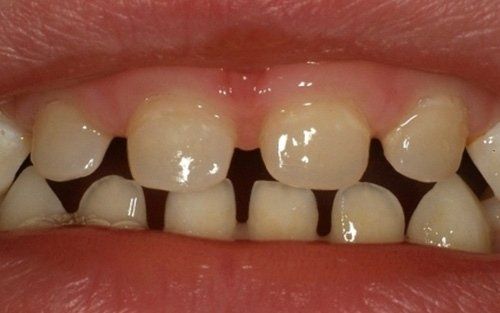

La carie nel bambino è una delle principali cause, insieme all’ortodonzia, di richiesta di intervento del dentista. La patologia ha una evoluzione particolarmente rapida in virtù della scarsità di smalto a difesa del dente da latte. Ciò comporta che, dal momento in cui il dente si ammala a quello in cui ne viene coinvolta la polpa (ovvero il nervo), il tempo sia veramente poco (vedi anche endodonzia pediatrica).

Spesso i dentini da latte cominciano a cariarsi già appena erompono nel cavo orale in quanto sono frequentemente a contatto con zuccheri semplici, come quelli veicolati dal biberon. Particolarmente aggressivi per i denti da latte risultano: tutte le tisane/infusi in commercio in bustine già pronte e pre-zuccherate; il latte zuccherato con qualsivoglia tipologia, incluso il miele; il latte e biscotti, specie nell’uso notturno; l’utilizzo quotidiano, spesso al posto dell’acqua, di succhi di frutta o bevande acide, per citare alcuni fra i più comuni errori commessi nel tentativo di dare una alimentazione completa al bambino, che spesso si traduce nella comparsa di una patologia chiamata